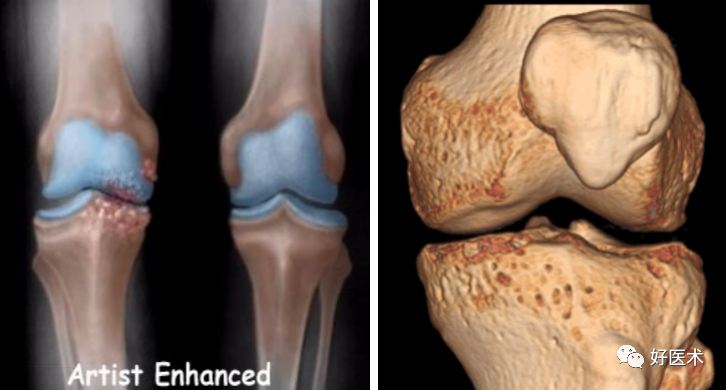

DR

-

CT

MRI

X线照片无法显示。

CT亦无法显示韧带、半月板等结构。

某些骨折对诊断前交叉韧带损伤有意义!